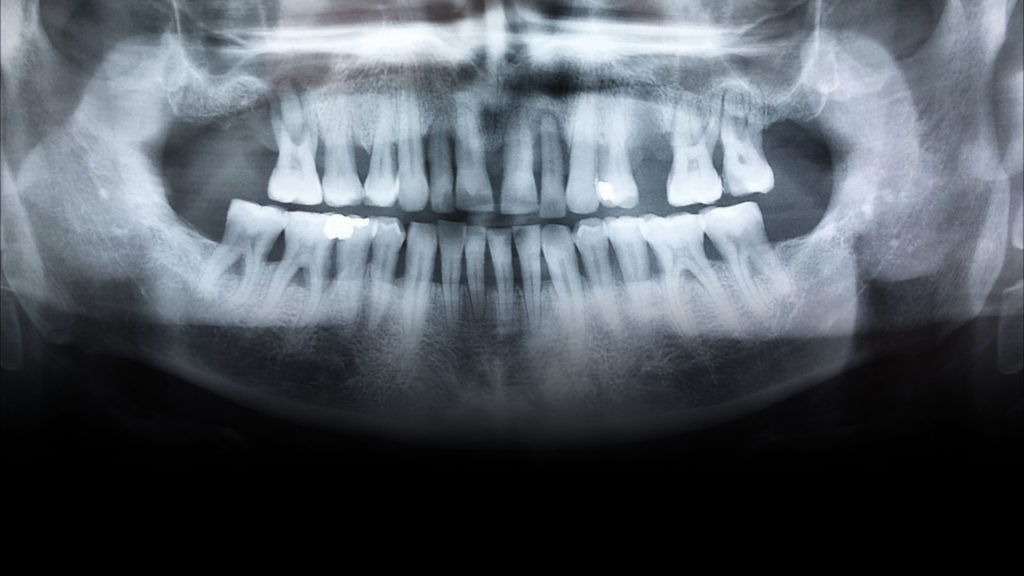

Bei dem Patienten handelte es sich um einen 49-jährigen Mann, Raucher (mehr als eine Packung pro Tag), mit einer Parodontalerkrankung, die vor drei Jahren diagnostiziert und behandelt worden war. Er wurde wegen des plötzlichen Verlusts seines Zahns 25 in der Klinik vorstellig. Im Rahmen der Untersuchung wurde zudem ein Mobilitätsgrad 3 an Zahn 22, aber auch an Zahn 12 konstatiert. Um den fehlenden Zahn 25 zu ersetzen, wurde ein Implantat in Betracht gezogen. Im Verlauf der weiteren klinischen Untersuchung wurden harte und weiche Konkremente und drei Amalgamfüllungen festgestellt. Ein näheres Screening und die Sondierung ergaben, dass weder Parodontaltaschen noch eine aktive Parodontalerkrankung vorlagen. Der Patient wurde über seine Situation informiert und eine Panoramaröntgenaufnahme angefertigt (siehe Abb. 1). Um zusätzlich zu prüfen, ob eine Implantation risikofrei durchführbar wäre und wie es um die Prognose bestellt sein würde, war auch eine DVT indiziert. Zudem wurde der Patient über die Risiken des Rauchens und die damit verbundenen möglichen Komplikationen sowie den Status der Parodontalanamnese aufgeklärt. Die Panoramaröntgenaufnahme zeigt die Merkmale einer älteren parodontalen Vorerkrankung. Die Alveole des Zahns 22 wies keinen Kontakt zum Knochen und Zahn 12 nur noch Knochen um den Apex herum auf (Abb. 1). Bei der Auswertung der DVT-Aufnahme wurde hinsichtlich der Länge und Breite ein gutes Knochenangebot für eine Implantation festgestellt, sodass der Zahn 22 extrahiert und in dieser Region implantiert werden konnte. Es wurde daher beschlossen, neben dem Zahn 25 – wegen dessen Verlusts der Patient die Praxis ursprünglich konsultiert hatte – auch den Zahn 22 implantatprothetisch zu rekonstruieren. Die prothetische Herausforderung im ästhetisch sichtbaren Bereich ist der Grund dafür, in diesem Artikel lediglich die Versorgung des Implantats in regio 22 zu beschreiben. Inseriert werden sollte dort ein Sweden & Martina Premium One-Implantat mit einem Durchmesser von 4,25 und einer Länge von 11,5 mm. Für ein bestmögliches Implantationsergebnis wurde das Implantat sofort nach der Extraktion des hochmobilen und als nicht erhaltungswürdig eingestuften Zahns 22 inseriert. Die Vorteile der Sofortimplantation wurden erstmals von Prof. Dr. Willi Schulte von der Universität Tübingen beschrieben. Der verbliebene Raum zwischen der Extraktionsalveole und dem Implantat wurde mit einer anorganischen porcinen Knochenmineral-Matrix (MinerOss XP, Camlog) mit dem Volumen 0,5 aufgefüllt. In der Abbildung 2 ist die Situation nach Insertion des Schweden & Martina Premium One-Implantats dargestellt. Nach vier Monaten Einheilzeit waren die Gewebe bereit und der Patient konnte definitiv versorgt werden.